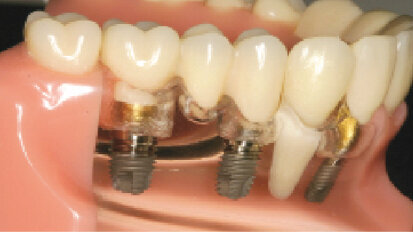

Náhrada nesená implantáty s využitím technologie teleskopů. Liviu Steier hovoří o hybridních protézách nesených implantáty

V současné době se díky očekávané větší délce života dostává do povědomí ...

Inovativní technologie ve zhotovování náhrad na implantáty – budoucnost je tady již dnes

Implantologie se v průběhu let neustále vyvíjí a je jednou z nejrychleji rostoucích oblastí naší profese....

Zjednodušená metoda snímání cementovaných prací na implantátech

Čas od času je nutné sejmout protetickou práci nacementovanou na jednom nebo více implantátech a ne vždy lze použít ...